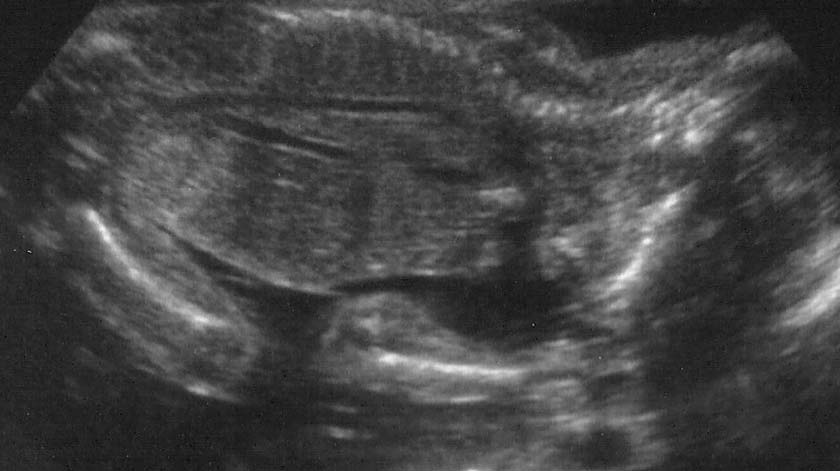

Via het UMC Amsterdam hebben we 10 setjes modelletjes aangeschaft en er zitten nog een aantal in de pijplijn. Dank aan de donateurs die dit mogelijk maakten. Deze handgemaakte modellen laten de ware grootte zien van ongeboren kinderen van zes, tot en met tien weken zwangerschap (gerekend vanaf de eerste dag van de laatste menstruatie). Zo kunnen wakers tijdens een gesprek laten zien hoe groot het kindje van de vrouw is en hoe het er uitziet. Het Fiom toont daarentegen op de website alleen een pluizig vruchtzakje als beeld van wat er zichtbaar is na de curettage als al het bloed, vocht en zacht weefsel is weggespoeld. Het UMC, laat de inhoud van het vruchtzakje zien. Het is maar welke boodschap je liever overbrengt.